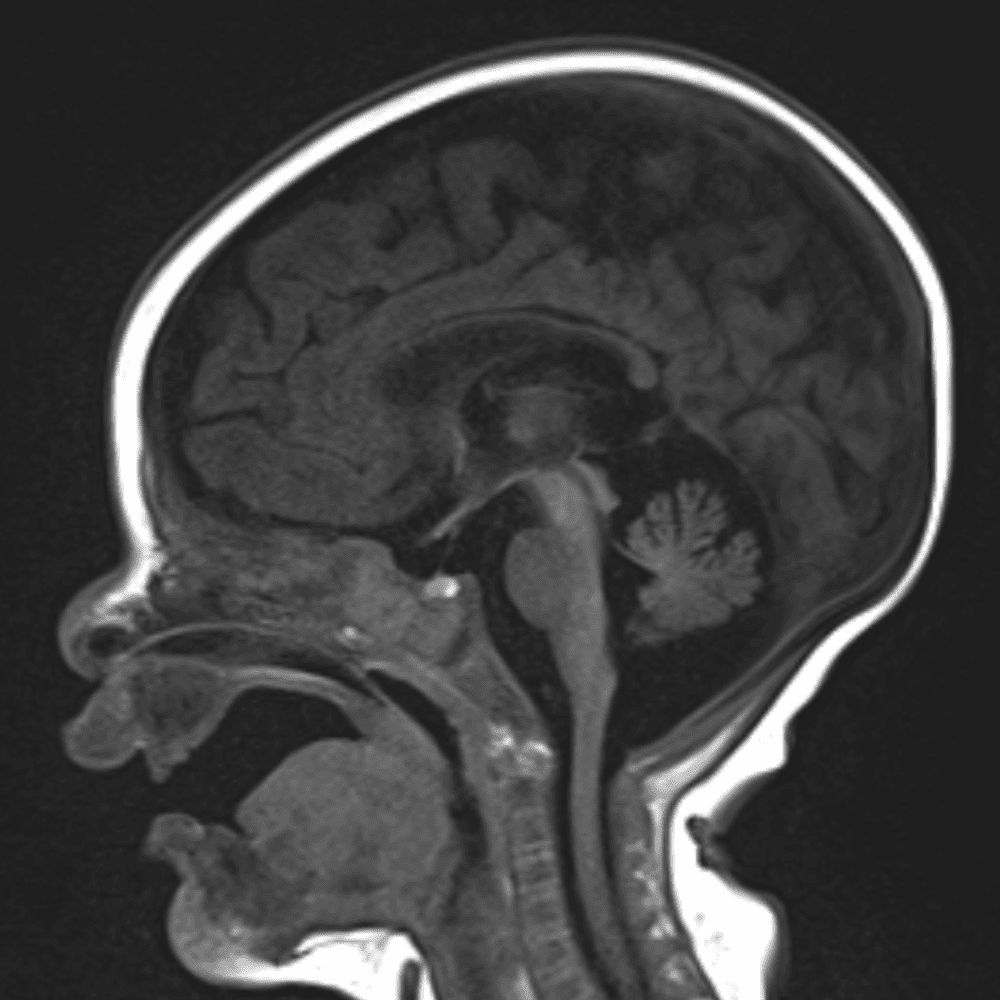

๋‹น์ง ์‹œ ํ”ํžˆ ๋ณผ ์ˆ˜ ์žˆ๋Š” ์‚ฌ๋ก€์˜ ์ „ํ˜•์ ์ธ ์˜ˆ๋ฅผ ํฌํ•จํ•ฉ๋‹ˆ๋‹ค.

39 ์‚ฌ๋ก€

์—ฐ์Šต

๋ฏธ๋ฌ˜ํ•˜๊ฑฐ๋‚˜ ์–ด๋ ค์šด ์‚ฌ๋ก€์™€ ์ผ๋ถ€ ์ •์ƒ ์‚ฌ๋ก€๋ฅผ ํฌํ•จํ•˜์—ฌ ๋‹น์ง์„ ์‹œ๋ฎฌ๋ ˆ์ด์…˜ํ•ฉ๋‹ˆ๋‹ค.

50 ์‚ฌ๋ก€